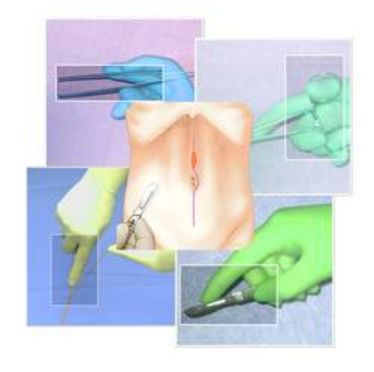

BASIC SURGICAL SKILLS

BASIC SURGICAL SKILLS

BASIC SURGICAL SKILLS

BASIC SURGICAL SKILLS

BASIC SURGICAL SKILLS

BASIC SURGICAL SKILLS